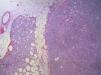

Presentamos el caso de una mujer de 40 años, sin antecedentes de interés, que consulta por palpación de nódulo mamario. La mamografía muestra una lesión nodular, bien delimitada, heterogénea, de 34mm, en el cuadrante superoexterno/prolongación axilar derecha. Se estudia mediante biopsia guiada por ecografía, con resultado de tumor mesenquimal con estroma mixoide, patrón vascular plexiforme y ocasionales células compatibles con lipoblastos. Con este diagnóstico se procede a la exéresis total de la lesión, que a la sección macroscópica muestra nódulo de bordes expansivos, de aspecto gelatinoso y características microscópicas de liposarcoma mixoide. Se presenta el caso y se revisa la literatura médica.

A 40 year old woman presented with a palpable swelling in her right breast. She had no relevant past medical history. Mammography revealed a 34mm, well-defined heterogeneous nodular mass in the axillary tail of the upper external quadrant of the right breast. An ultrasound guided biopsy was performed, in which a mesenchymal tumour was found, with myxoid stroma, a plexiform capillary pattern and scattered cells that resembled lipoblasts. Subsequently, the tumour was excised. Macroscopy showed regular margins on the cut surface and a myxoid lesion. Microscopically the lesion was diagnosed as myxoid liposarcoma. The clinico-pathological features of the case are described and the pertinent literature discussed.